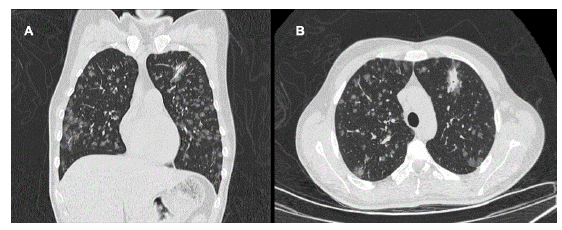

Se consideró paciente inmunocomprometido con compromiso respiratorio y cutáneo, quien no cumple criterios de caso sospechoso de SARS-COV2; se indicó realizar Tomografia de Tórax de Alta Resolucion (TACAR) para evaluar lesiones a nivel intersticial; además, toma de baciloscopias seriadas y Genexpert para descartar tuberculosis. Se solicitaron paraclinicos de extension para valorar respuesta inflamatoria sistémica, función renal, función hepática y estado hidroelectrolítico; los cuales evidenciaron LDH y fosfatasa alcalina elevadas, elevación de transaminasas sin alteraciones en ecografía hepatobiliar a excepción de leve esplenomegalia y perfil hepatotropo negativo, hipoalbuminemia, hiponatremia leve, sin elevación de azoados, bicitopenia dada por anemia moderada microcítica hipocrómica heterogénea con ferropenia asociada y leucopenia leve (ver Tabla 1). En la TACAR se observó el parénquima pulmonar con múltiples lesiones de características nodulares, hallazgos pulmonares sugestivos de origen inflamatorio infeccioso (ver Figura 2). Ante hallazgos imagenológicos fue llevado a fibrobroncoscopia con lavado alveolar en el que se aísla histoplasma. En lo referente al compromiso dermatológico, incialmente con sospecha de Sarcoma de Kaposi, por lo que se realizó biopsia de piel que lo descartó y que reportó estudios con tinciones de PAS y Gomori-Grocott en la que se observaron estructuras micóticas compatibles con histoplasma (ver Figura 3). Adicionalemnte, dado síntomas del estado de ánimo, se solicitó valoración por psiquiatría y psicología quienes consideraron cursando con trastorno adaptativo, descartaron requerimiento de psicofármacos y realizaron seguimiento durante la hospitalización.

Figura 2 Tomografía de Tórax de Alta Resolución. Corte Coronal (A), Corte Axial (B). En el parénquima pulmonar se identifican múltiples nódulos de distribución difusa en vidrio despulido asociado a engrasamiento septal con patrón en empedrado, identificándose una consolidación periférica con extensión peribroncovascular en el segmento anterior del lóbulo superior izquierdo asociado a signo del halo.